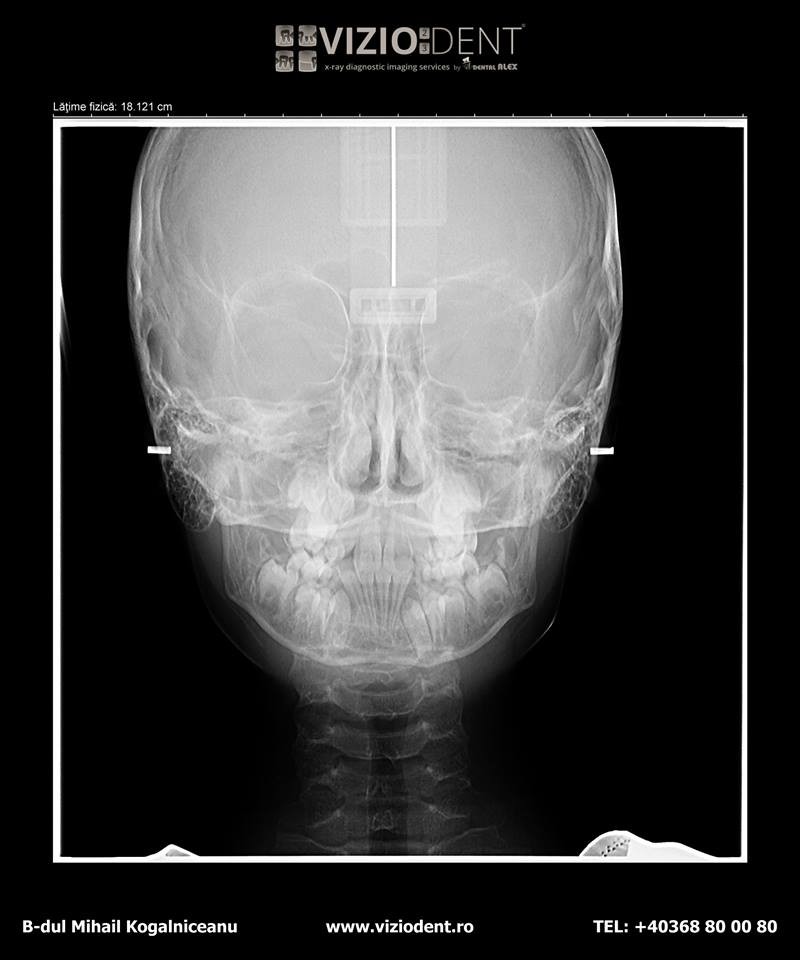

- teleradiografie ant/post